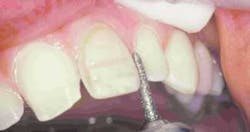

Preparation of the four incisors was then initiated using diamond burs from the Shofu Contemporary Cutting Kit (Figure 5). With the high-speed ElectroTorque KaVo handpiece, a small round diamond (0872-1) was used to outline the peripheral margins of the preparations (Figure 6). By scoring the facial surface of the incisors with the depth cutter (0897-1) (Figure 7), smooth and uniform tooth structure removal using a coarse tapered diamond (0835C-1) was facilitated (Figure 8). As tooth nos. 9 and 10 were prepared, it came time to address the gingival contour issues of the inflamed interproximal gingiva.